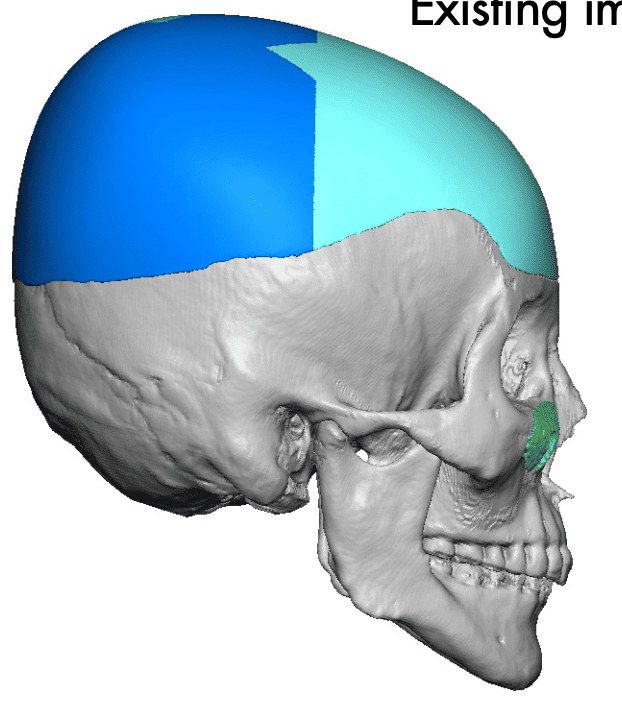

Desire for head shape asymmetry improvement as the final stage of total skull reshaping surgeries. (previous skull implants are in green color)

Placement of custom temporal implant through an incision behind the ear.

Desire for head shape asymmetry improvement as the final stage of total skull reshaping surgeries. (previous skull implants are in green color)

Placement of custom temporal implant through an incision behind the ear.